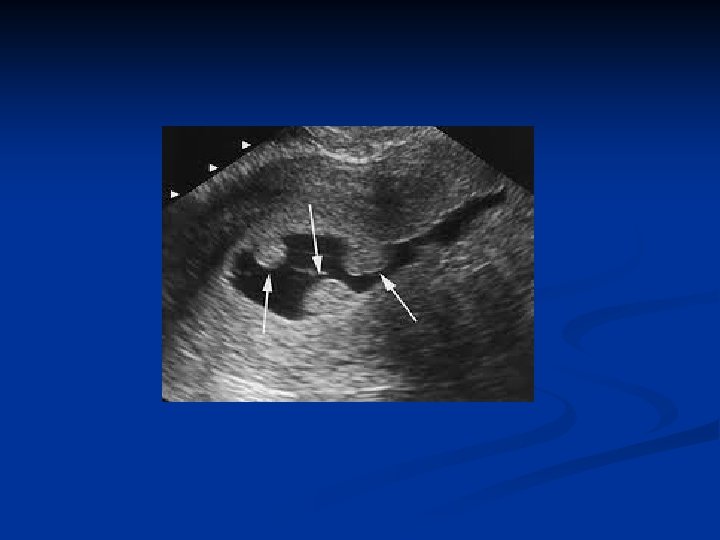

Adenomyosis n n Is defined by the presence of endometrial glands and stroma within the myometrium Can be diffuse or localised ( adenomyosis) Incidence is 20% Pathogenesis is unkown n Might be sec to postpartum endometritis because of the endom line break down An arrest of Mullerian cells in the myometrium and later de nova endometrial gland development Animal models suggest PRL and FSH stimulates growth

Adenomyosis n Symptoms and signs n n n Menorrhagia Dysmenorrhea Treatment n n Hysterectomi Gn. RHa